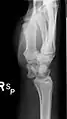

The lunate bone is the most frequently dislocated carpal bone.

Dislocated lunate